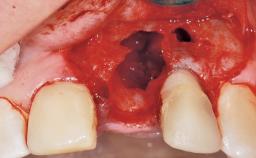

Early Placement of an Implant in a Maxillary Right Central Incisor Site

This 41-year-old female patient was referred to the clinic for the replacement of the right central incisor, since the tooth had developed a root fracture in the long axis that made extraction necessary. The healthy, non-smoking patient was first seen with the tooth still in place. A detailed Esthetic Risk Assessment was performed.The patient was worried about her dental esthetics and had high expectations for a successful treatment outcome from an esthetic point of view. The patient had a medium lip line that displayed parts of the gingiva in the anterior maxilla upon smile.

Bone Volume Deficient horizontally, allowing simultaneous augumentation

Esthetic Risk High